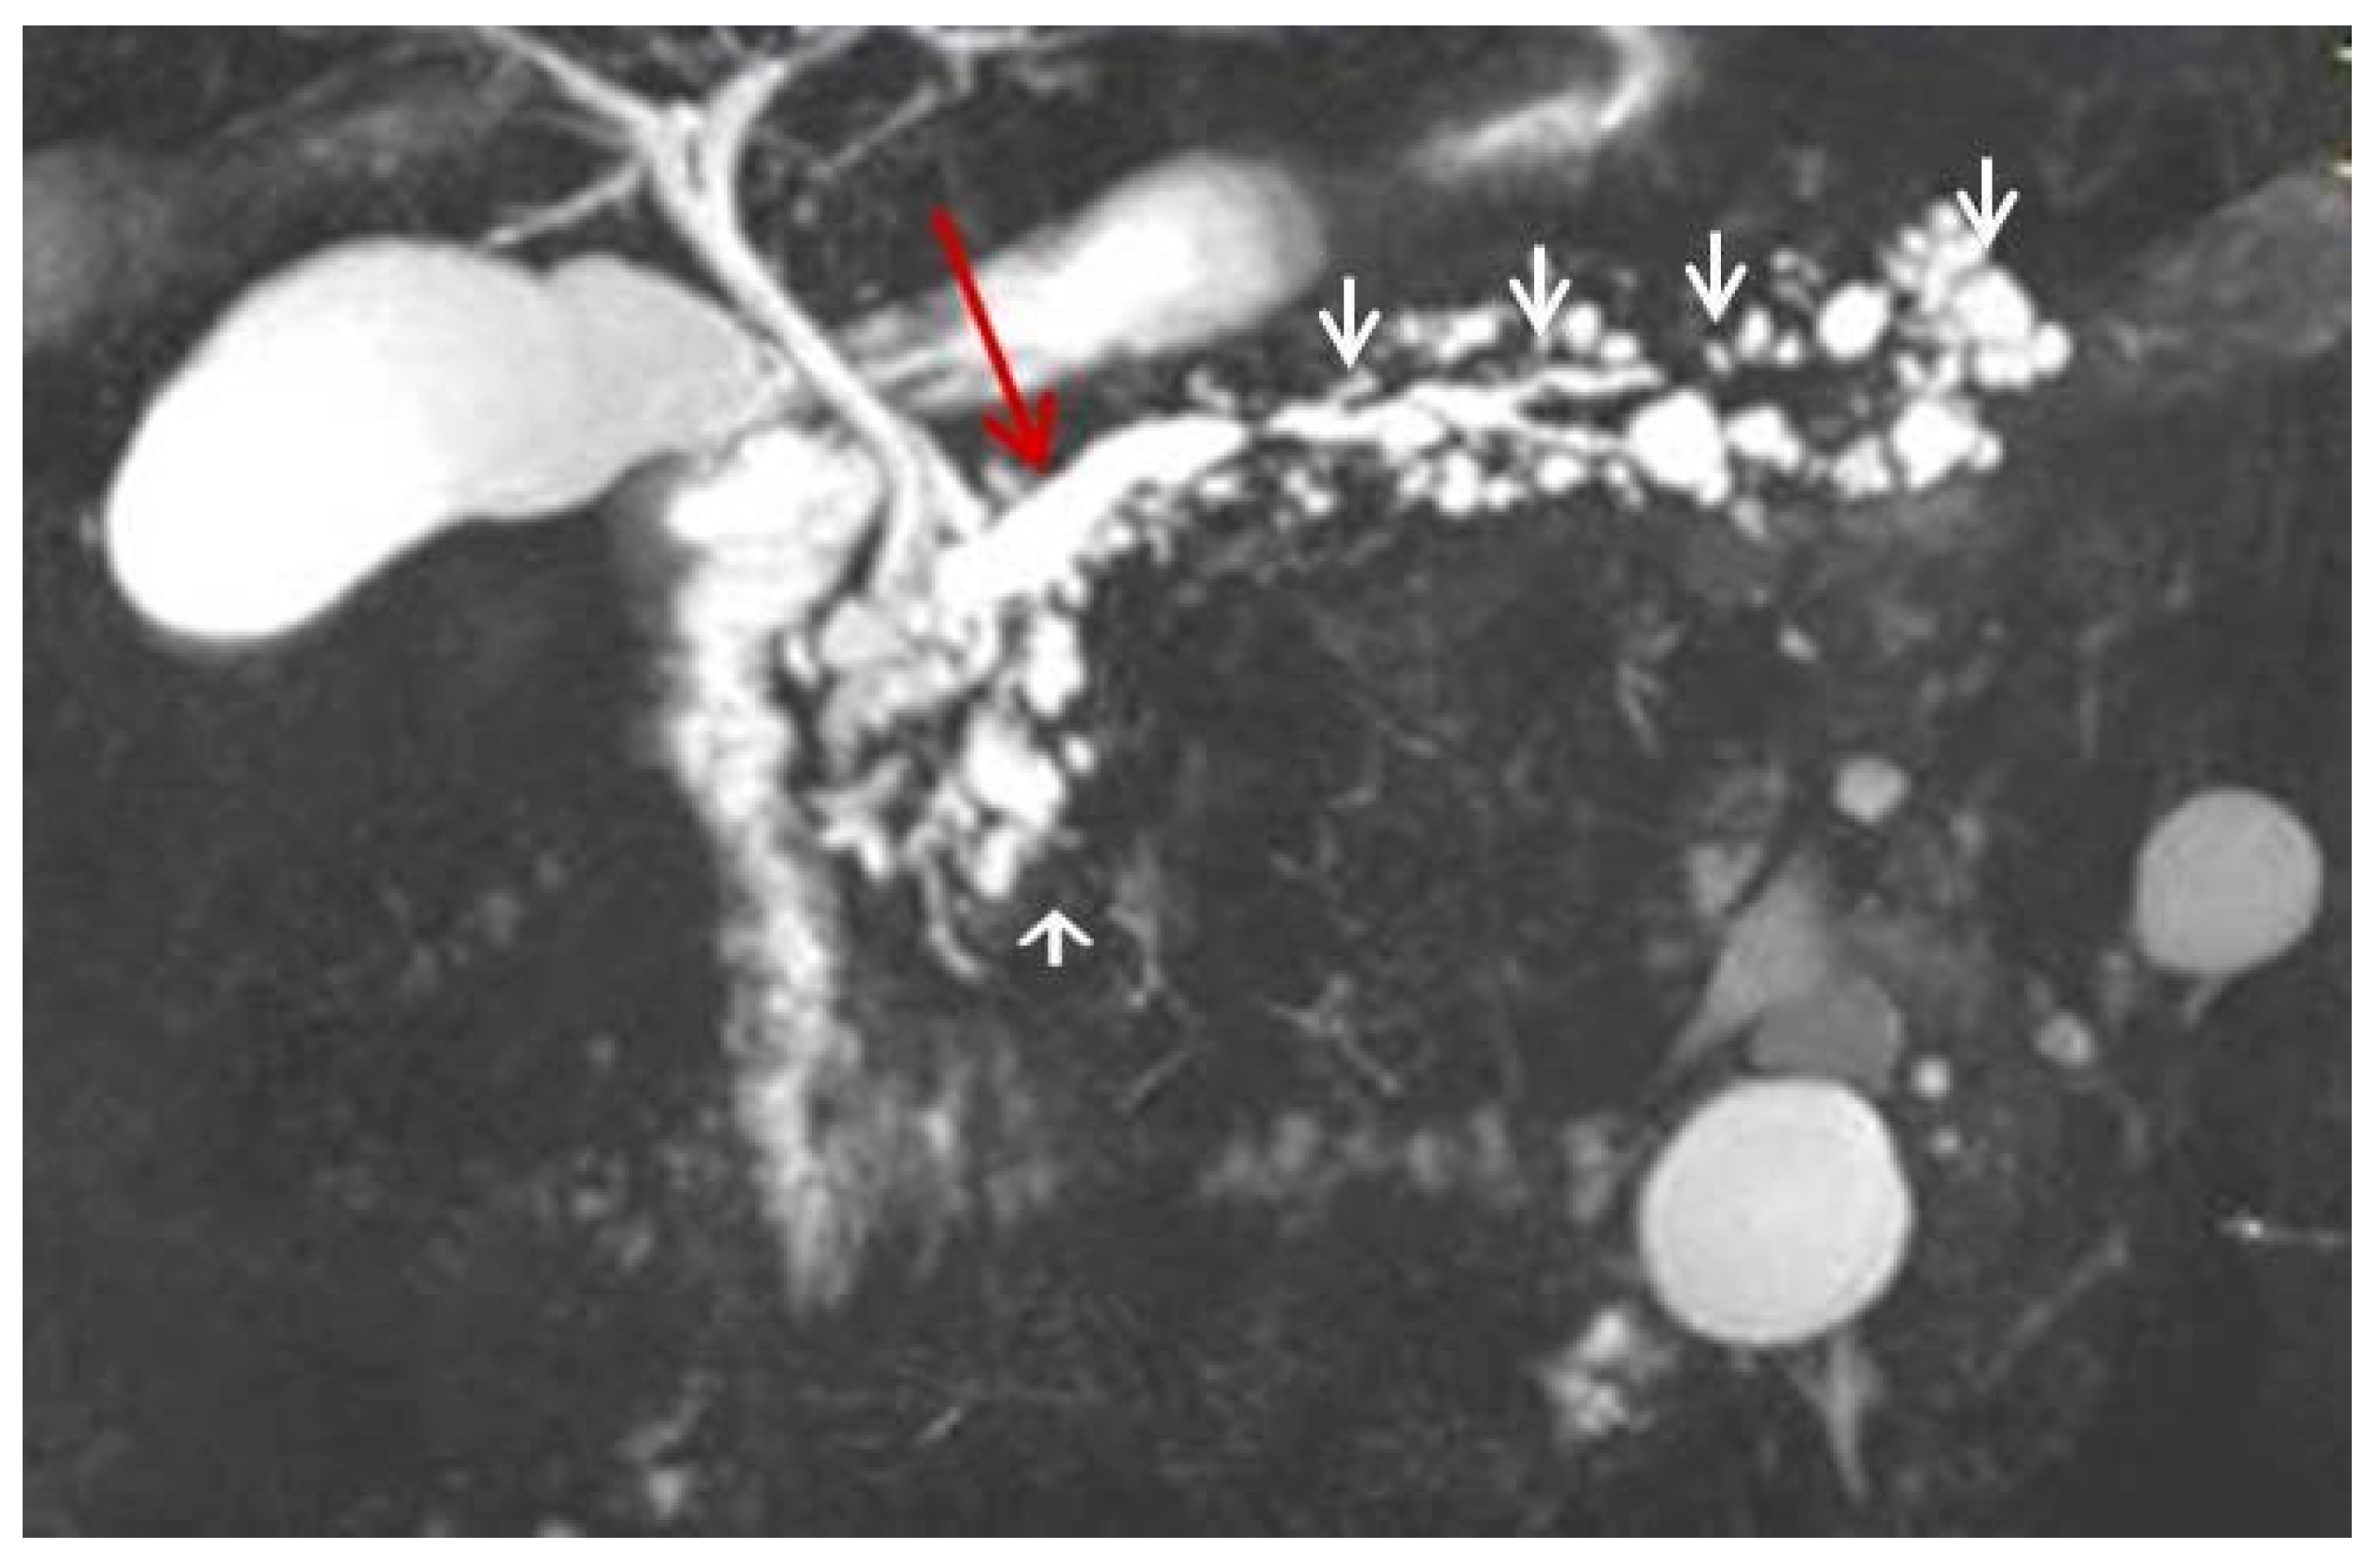

2. Case Report